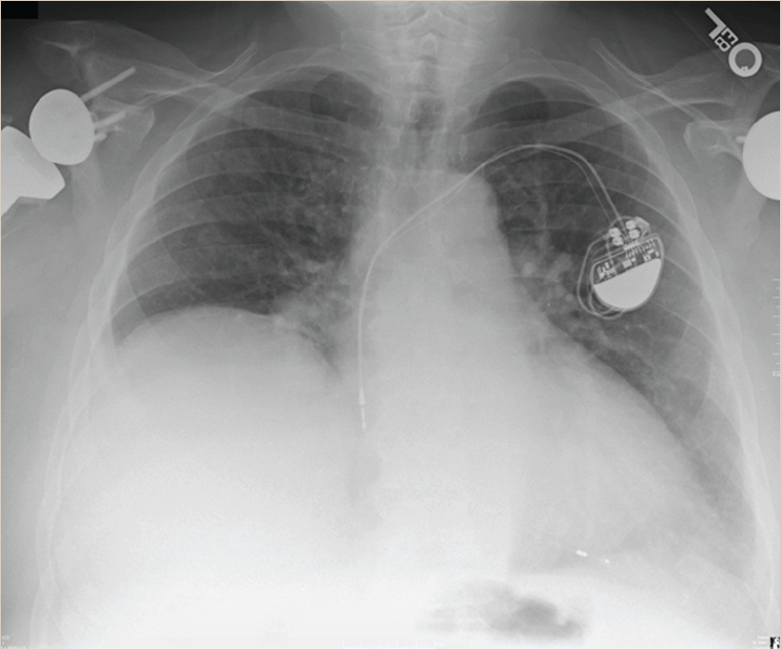

Elevated hemi diaphragm, Chest x ray, causes paralysis or eventration ? YouTube Can The Diaphragm Be Damaged Phrenic nerve damage can cause your diaphragm to stop working properly, making it hard to breathe and live normally. Learn about the causes, symptoms and treatments of diaphragm paralysis, a condition that affects breathing and is often caused by. Traumatic injury to the diaphragm is rare. Learn about the causes, symptoms,. A tight diaphragm can cause pain in the side,. Can The Diaphragm Be Damaged.

Case 3 An 11monthold male with right diaphragmatic paralysis. Chest... Download Scientific Can The Diaphragm Be Damaged Learn about the causes, symptoms,. Learn about the causes, symptoms and treatments of diaphragm paralysis, a condition that affects breathing and is often caused by. A tight diaphragm can cause pain in the side, chest, neck, and shoulders, as well as shortness of breath, hiccups, and indigestion. Traumatic injury to the diaphragm is rare. Learn about the possible causes of. Can The Diaphragm Be Damaged.